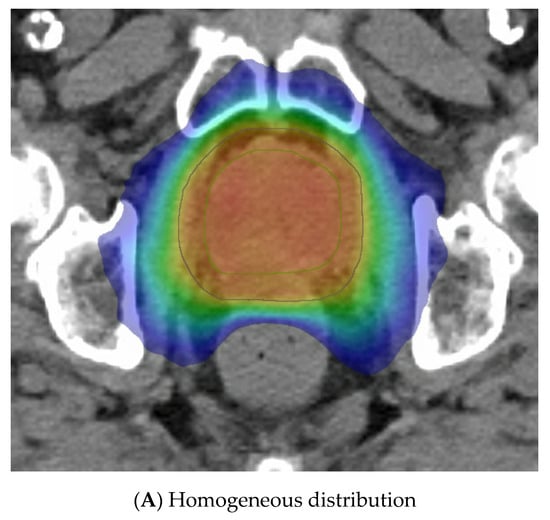

The last variable is the dose distribution, which varies between centres and trials. Some methods employ a relatively homogeneous whole-gland dose distribution (Figure 3A), whereas others aim to introduce inhomogeneity to replicate a brachytherapy implant with the purposeful aim of creating “hotspots” within defined volumes to receive up to 150% of the prescribed dose. These virtual volumes are intended to direct hotspots towards brachytherapy-type structures, such as spheres or cylinders. The CK platform can better replicate a virtual cylinder dose distribution compared to a standard LINAC due to the large number of non-coplanar angles used during delivery. A “hot shell” distribution aims to create hotspots along the prostate periphery with central urethra cooling (Figure 3B).

Figure 3.

Examples of virtual high-dose-rate brachytherapy boost radiotherapy dose distributions, with the colour gradient demonstrating 50% of the dose in blue up to the maximum doses in red. The green outline represents the prostate, the blue outline the planning target volume (PTV), yellow is the urethra, and burgundy the DIL, when outlined. (A) Homogenous distribution with 100% of the dose in red. (B) Hot-shell distribution showing the red 150% dose directed towards the prostate peripheral zone, with lime being the 100% dose. (C) Dominant intraprostatic lesion distribution, with the 150% dose in red directed towards the DIL and 100% dose in lime covering the PTV.

Another method gaining traction due to the FLAME RCT [66] is dominant intraprostatic lesion (DIL) boosting, where the boost dose is concentrated in the image-defined cancer volume (Figure 3C). FLAME used a simultaneous integrated boost and delivered a dose of up to 95 Gy in 35 fractions to the MRI DIL, with the whole prostate gland receiving 77 Gy in 35 fractions. A total of 84% of these patients were high risk and two thirds received ADT for up to 3 years. This trial reported improved 5 year biochemical disease-free survival (bcDFS), increasing from 85% to 92%, in the boost arm (HR: 0.45, 95% CI: 0.28 to 0.71, p < 0.001) without any significant increase in late GI or GU toxicities. The BOOSTER trial [50] integrated DIL boost with vHDRB, with three dose levels given. After the conventional radiotherapy dose of 46 Gy in 23 fractions, the boost used 20 Gy, 22 Gy, or 24 Gy to the prostate and, correspondingly, 25 Gy, 27.5 Gy, and 30 Gy to the DIL, all in two fractions. The highest dose of 30 Gy in two fractions was modelled to reflect the 150% isodose distribution of an HDR plan but preferentially directed towards the DIL.